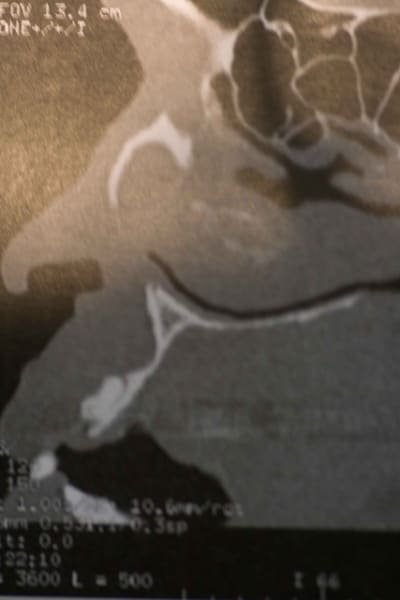

Il s'agit d'un patient africain avec une grosse lacune au dessus de la 22 . A savoir que le patient est en super bipro alveolie.

Asymptomatique totalement. Je sens une grosse dépression a la palpation.

Vous trouverez ici la video du scanner (entre 8 et 13 )

Bonjour, sur ton scan et sur ta pano on ne voit pas de continuité entre les apex et le defect osseux, pourquoi veux tu intervenir au niveau dentaire?

on dirait une lésion des tissus mous.

y'a-t-il moyen de récup les coupes pour faire notre propre analyse. c'est pas évident sur les seules coupes horizontales.

Le déplacement dentaire indique qu'il y a un processus tumoral sous-jacent, certainement bénin mais y'a quelque chose

après réflexion, ma première hypothèse serait un kyste naso-labial.

on dirait qu il y a des dents surnuméraires ou odontoides:

possible deux dans la lacune au dessus de 22 et voir au dessus de 12... voir 3D

A la palpation je sens une depression importante et pas une voussure c est pour ca que je pensais plus a une lesion idiopathique qu a un kyste congenital . Je vous post les coup antero post des que je suis au cabinet

toujours est-il que la topographie et la sémiologie radiologique sont compatibles avec le KNL.

genre une lacune de stafne du maxillaire (supérieur) ??? ch'ui pas franchement convaincu et reste sur mon analyse qui correspond à quelquechose qui est décrit même si on l'observe rarement.

Voila les coupes AP ( de mauvaise qualité c'est moi qui ai fait la photo).

A savoir qu'a la palpation je sens vraiment un "trou".